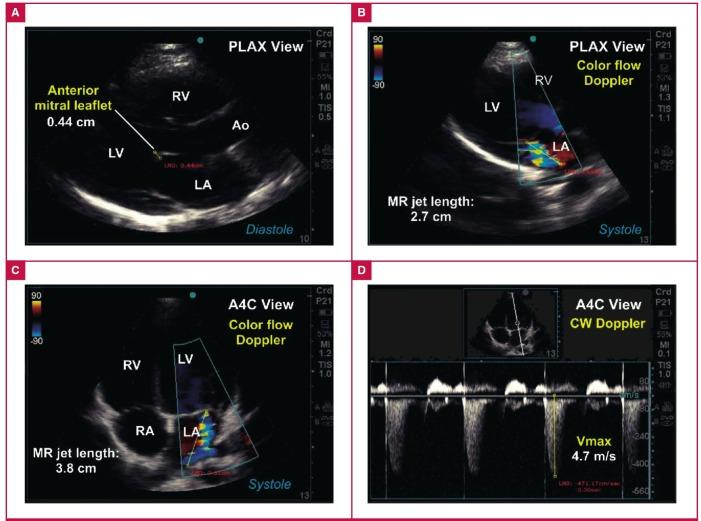

https://cdn.ncbi.nlm.nih.gov/pmc/blobs/c4d6/5730679/fa7d03f2eaa8/cvja-28-286-g001.jpg